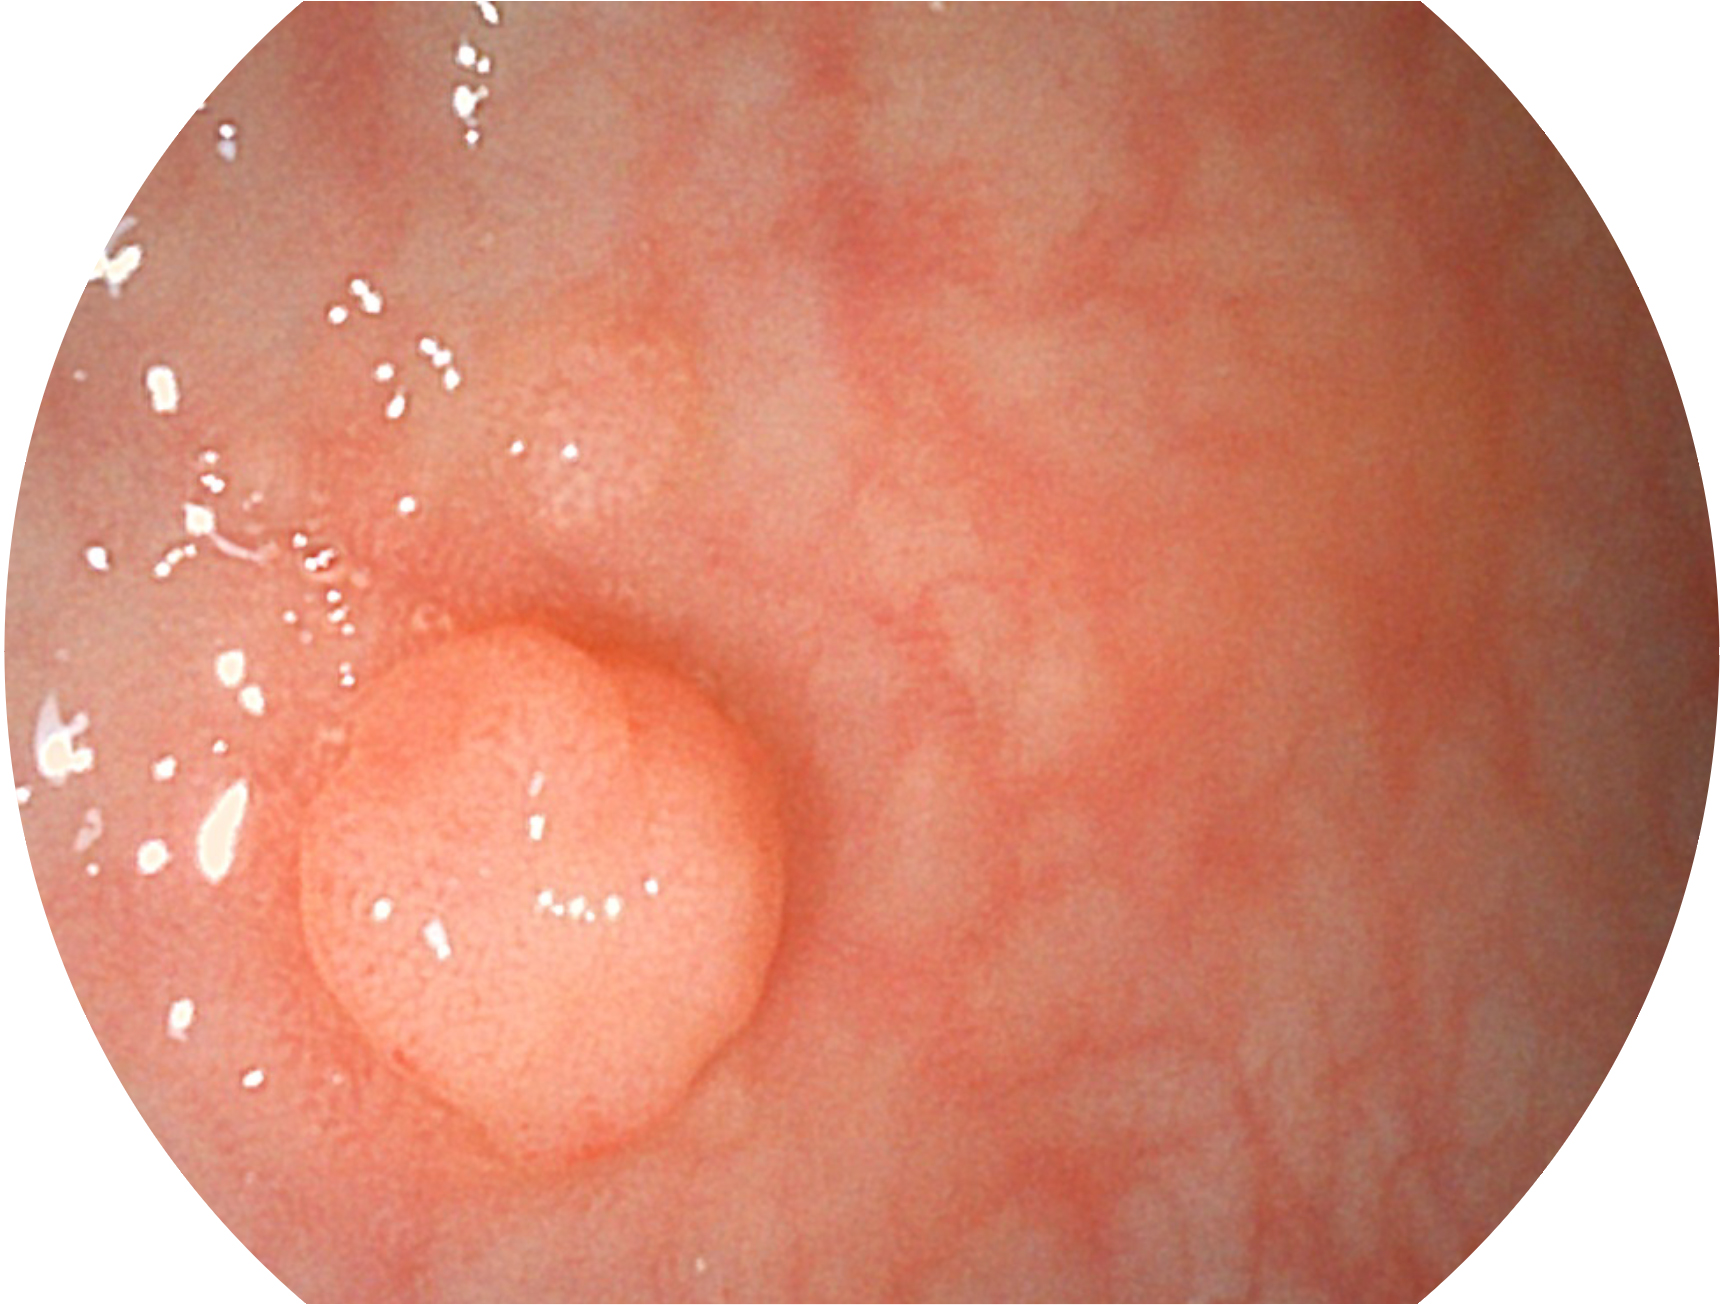

诸侯快讯官网新开发的内镜染色技术,主要是基于多波长LED 光源的开发,VLS-55Q 四波长LED 光源是由四个不同颜色的LED光按照相应照明模式所规定的特定发光比例进行合束后形成,合束后形成的照明光的光谱由红光、绿光、蓝光及蓝紫光这四个不同的波段范围构成。具有更高光谱自由度,通过光谱比例的控制,实现了聚谱成像技术,英文全称为“Spectral Focused Imaging, SFI”,缩写为“SFI”和光电复合染色成像技术,英文全称为“Versatile Intelligent Staining Technology, VIST”,缩写为“VIST”。